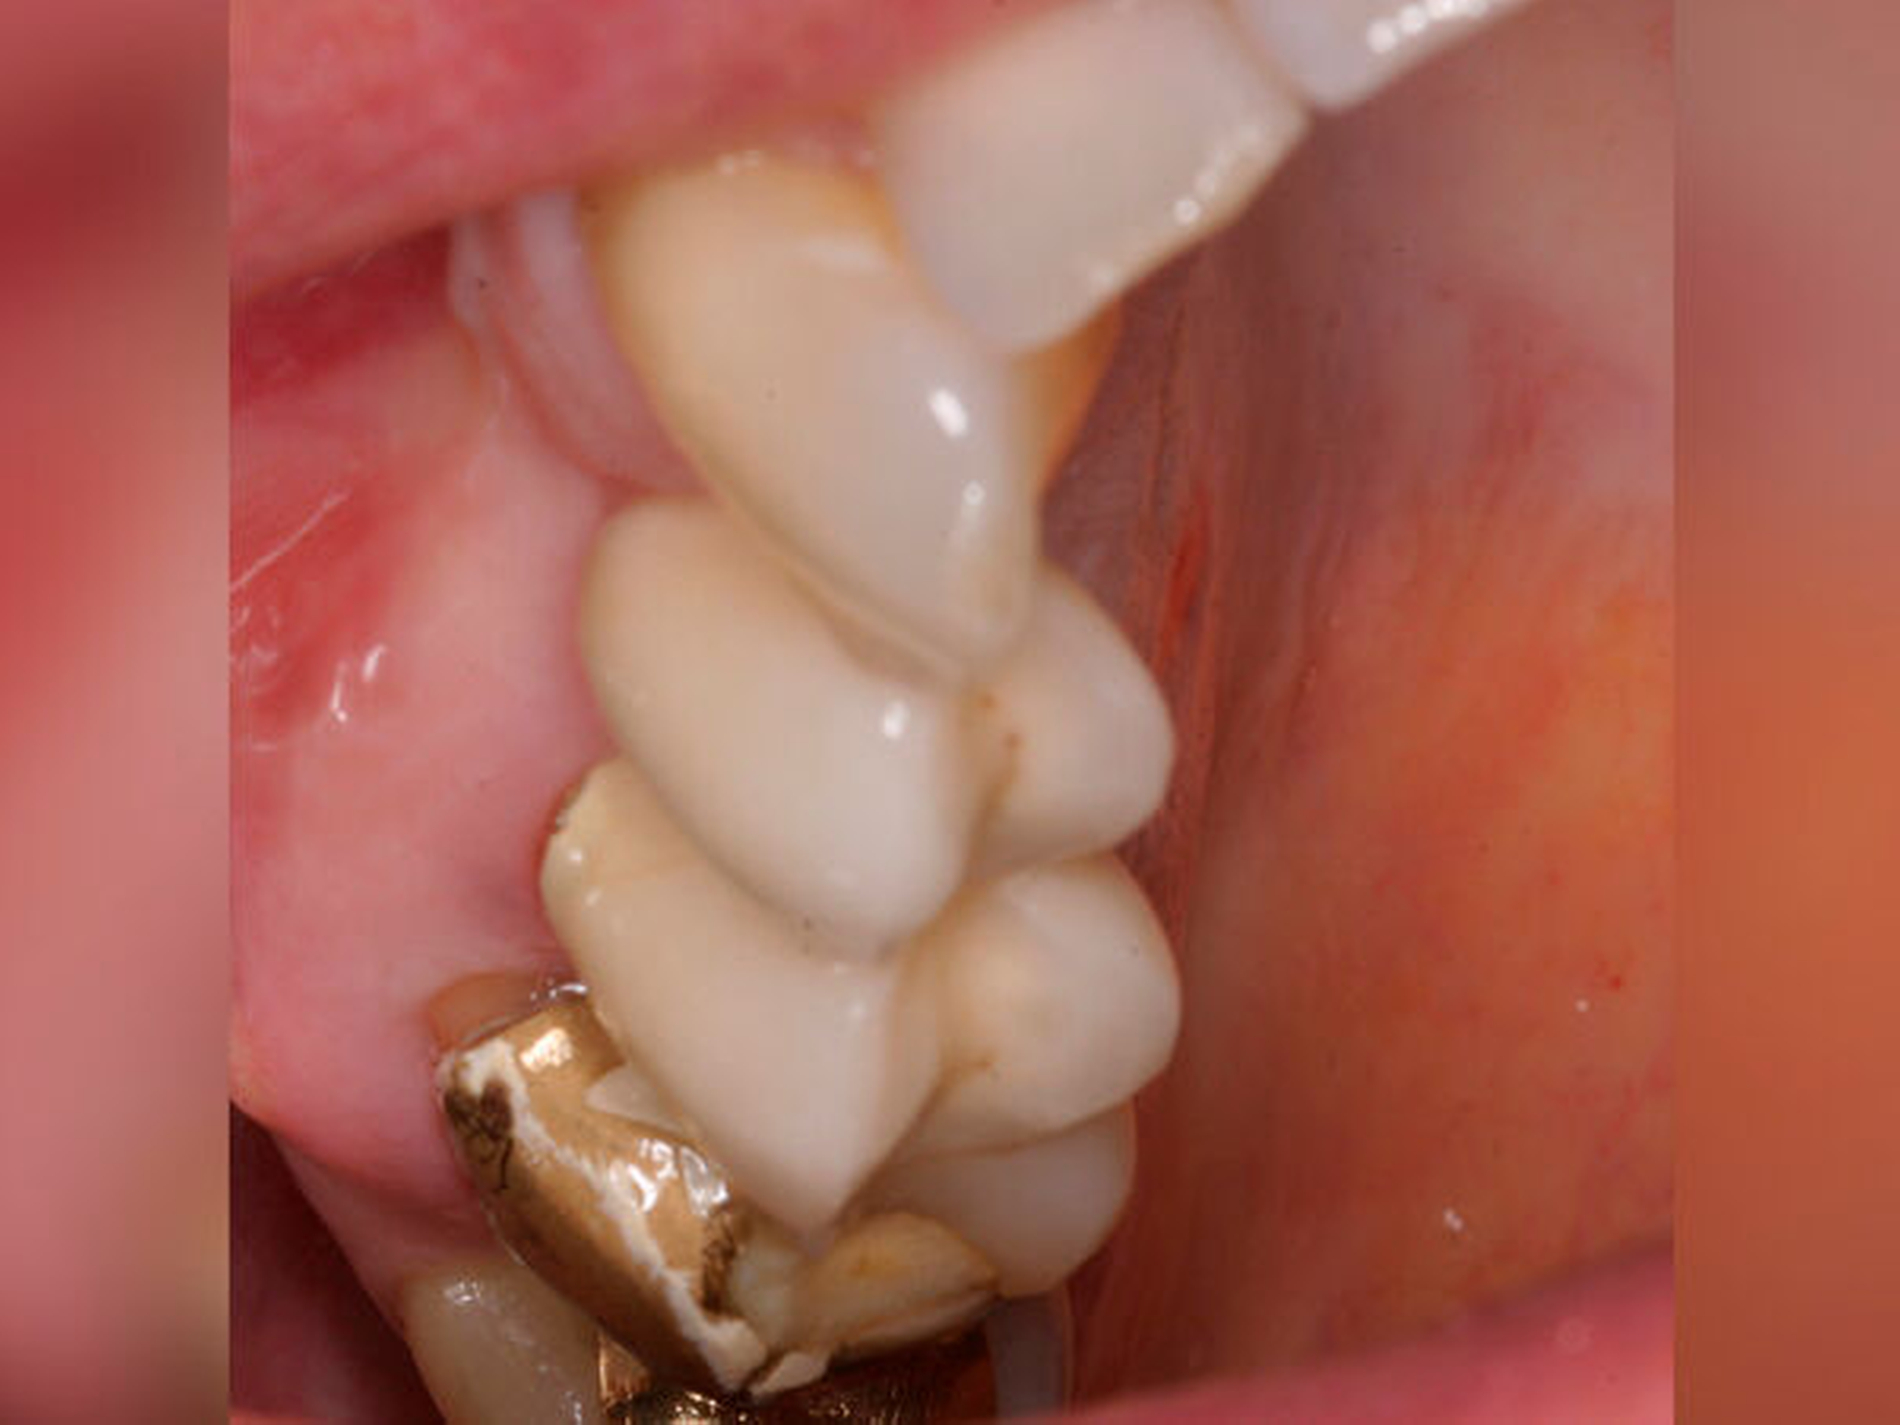

Eine 54-jährige Patientin stellte sich 2018 in der Praxis vor, nachdem sie beim Essen ein Goldinlay an Zahn 16 verloren hatte. Sie klagte über eine Aufbissempfindlichkeit des Zahnes sowie über das Gefühl einer Lockerung. Klinisch zeigte sich eine tiefe Fraktur des Zahnes in mesiodistaler Richtung. Nach klinischer und röntgenologischer Diagnostik wurde die Patientin über die Möglichkeit der Extraktion mit anschließender prothetischer Versorgung der Lücke und den aufwendigen Erhaltungsversuch mittels endodontischer Behandlung des Zahnes samt Amputation der palatinalen Wurzel aufgeklärt. Die Patientin war sehr motiviert und entschied sich für den Erhaltungsversuch.

So erfolgte nach endodontischer Behandlung des Zahnes die Amputation der palatinalen Wurzel und die Versorgung des Zahnes mit einer Vollkrone. Die Situation an 16 ist seitdem stabil, allerdings zeigen sich auch hier palatinal erhöhte Sondierungstiefen, die röntgenologisch mit einem progredienten Knochenabbau im Bereich der Furkation zu korrelieren scheinen. Die Patientin gibt an, mit der Reinigung des Zahnes keine Probleme zu haben, möglicherweise ist diese jedoch durch die Einziehung im Bereich der Furkation vor allem palatinal erschwert. Die Patientin wurde daraufhin instruiert, wie sie die häusliche Mundhygiene in den schwer zugänglichen Bereichen intensivieren und verbessern kann.